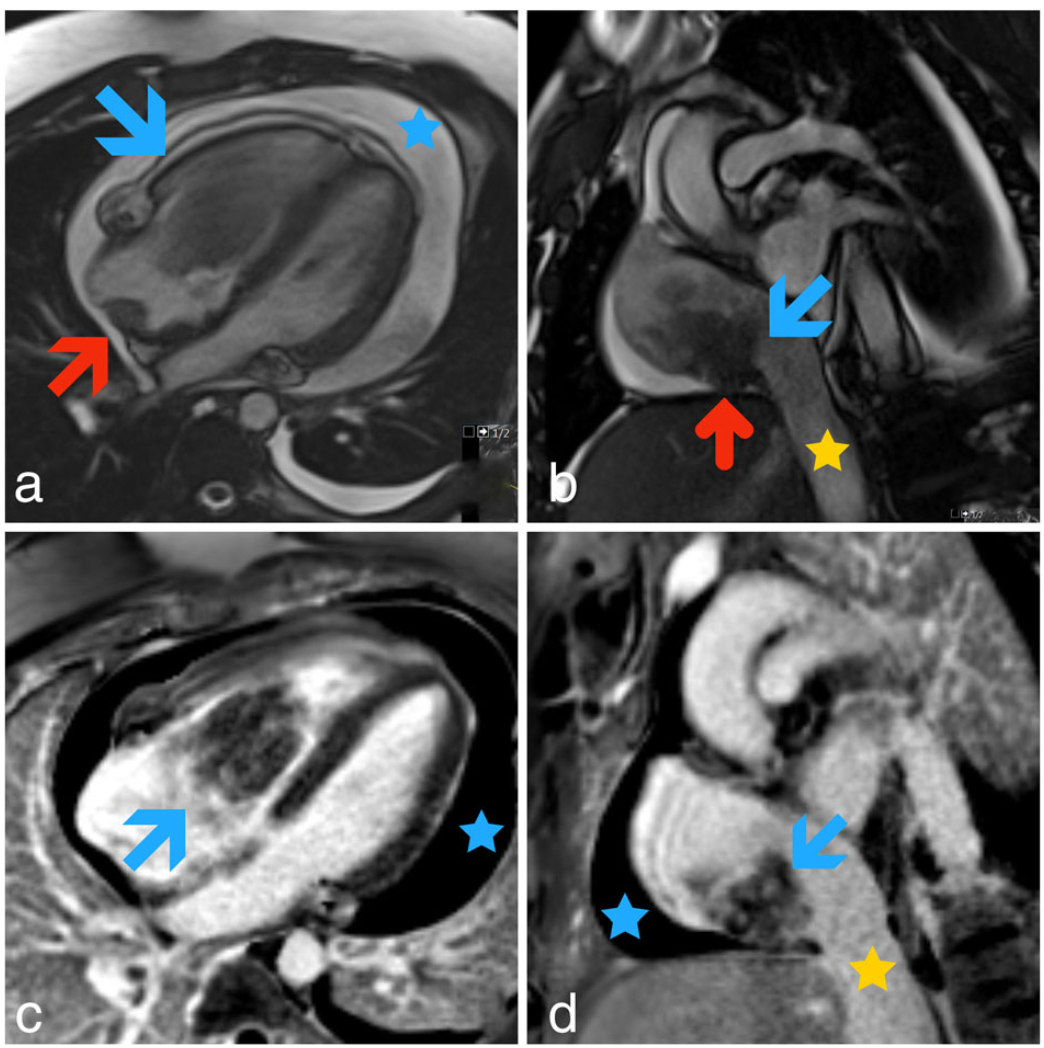

二维超声心动图显示一个7×3.6cm的回声团附着在右心房顶部,每跳动一次,它就会穿过右心室使三尖瓣脱垂。这一发现通过心脏共振成像进一步表现为一个巨大的叶状移动肿块(8.6×3.8cm),附着在右后下心房壁,心包扩张(图1)。

图1:(a)四室平衡稳态自由进动(bSSFP)心脏MRI图像显示一个位于右心房的巨大叶状肿块脱垂至右心室(蓝色箭头)。右心房后壁附着也显示出来(红色箭头)。(b)通过右心房基底的相应短轴bSSFP图像清楚显示肿块的下附着(蓝色箭头)以及向心包间隙的微小延伸(红色箭头)。(c和d)四室和两室相敏倒置恢复(PSIR)延迟增强显示肿瘤病灶(蓝色箭头)内的不均匀增强。黄色星号表示下腔静脉,蓝色箭头表示心包积液